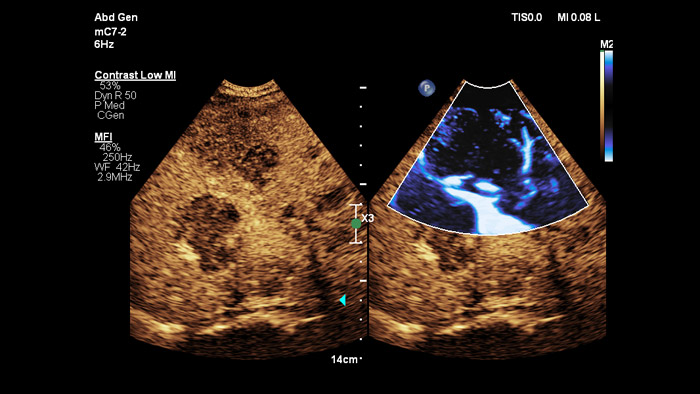

Jeder Mensch ist anders. Die PureWave Kristalltechnologie bietet ein verbessertes Eindringvermögen bei schwer schallbaren Patienten ohne Abstriche bei der Detailauflösung, der Doppler-Empfindlichkeit und dem kontrastmittelverstärkten Ultraschall (CEUS).

Die PureWave Kristalltechnologie ist der größte Durchbruch bei piezoelektrischem Schallkopfmaterial seit 40 Jahren und ist 85 % effizienter als herkömmliche piezoelektrisches Schallkopfmaterial, was zu herausragenden Ergebnissen bei unterschiedlichsten Patienten führt.